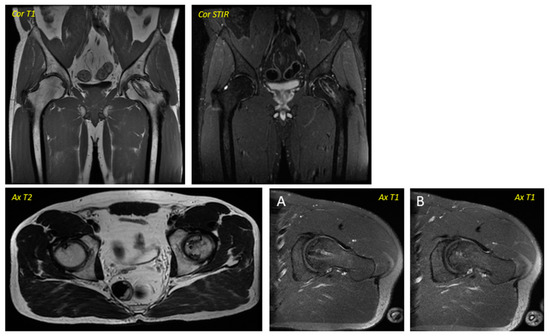

Figure 1. Pre-surgical image corresponding to a 38-year-old male performed in December 2013. The geographic area in the superior anterior region of the left femoral head is delimited by a hypointense line in T1 sequences and hyperintense in T2 sequences in relation to avascular necrosis. No loss of sphericity of the femoral head or joint effusion is evident. It corresponds to type II in the Association Research Circulation Osseous (ARCO) classification.

Regarding the imaging studies, several findings were observed in the radiographic evolution during the 12-month follow-up (Figure 1 and Figure 2). First, changes in the direction appeared in all cases from the sixth month, not being evident in earlier stages. Second, radiographic stabilization was achieved in 62.5% of the patients (n = 5) during the first year after surgery. Third, two patients (25%) showed the progression of the necrotic zone, while in one (12.5%), signs of re-ossification were evident. Despite observing descriptive differences, the p-value was not statistically significant for the latter parameter (p = 0.317).

Regarding the dynamics in the MR images, two patients were baseline in stage IA of the ARCO classification (25%), two in IIA (25%), and four in IIB (50%). In the same way, a stabilization in the staging of the post-surgery images was observed in seven of the eight patients studied (87.5%), with only one case (12.5%) evolving from grade IIB to grade IIIA, presenting subchondral collapse of the femoral head, which was already evident from the sixth month onwards. Descriptively, changes were observed, but they were not statistically significant. No significant variability was observed in the imaging findings between patients.